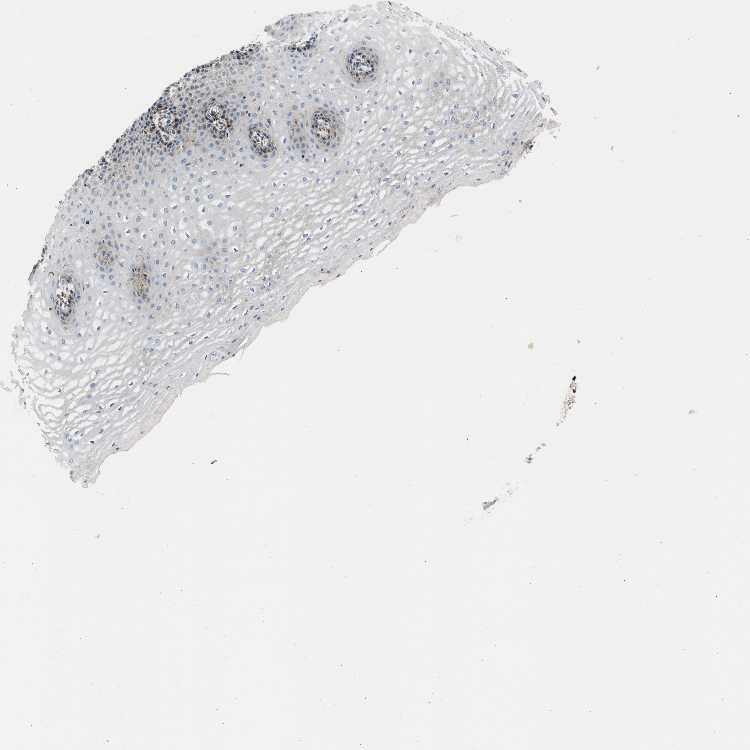

ESOPHAGUS - Antibody stainingi

Antibody staining in the annotated cell types in the current human tissue is reported as not detected, low, medium, or high, based on conventional immunohistochemistry profiling in selected tissues. This score is based on the combination of the staining intensity and fraction of stained cells.

Each image is clickable and will lead to virtual microscopy that enables deeper exploration of all samples and also displays staining intensity scores, fraction scores and subcellular localization as well as patient and tissue information for each sample.

Antibody HPA020233

Squamous epithelial cells Low